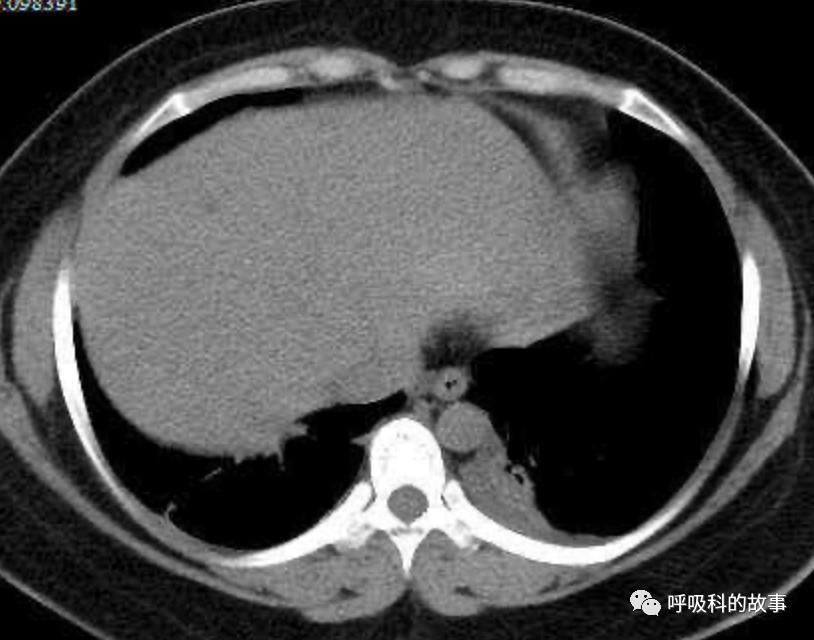

上面三张图分别是第一、二、三周的体温单

患者发热后行胸部CT检查(6月21日,住院第13天),可见两下肺有条片影,当时考虑是肺炎引起的发热。

可是在6月26日(往院第18天)仍持续发热的情况下复查肺部CT,肺部病灶已明显吸收了。那么患者发热的原因到底是什么呢?为什么患者高热的情况下血白细胞不升反降,C反应蛋白也没有明显增高?这个时候消化科医生也迷茫了,这可怎么办?于是请感染科和呼吸科医生一起会诊,共商计策。